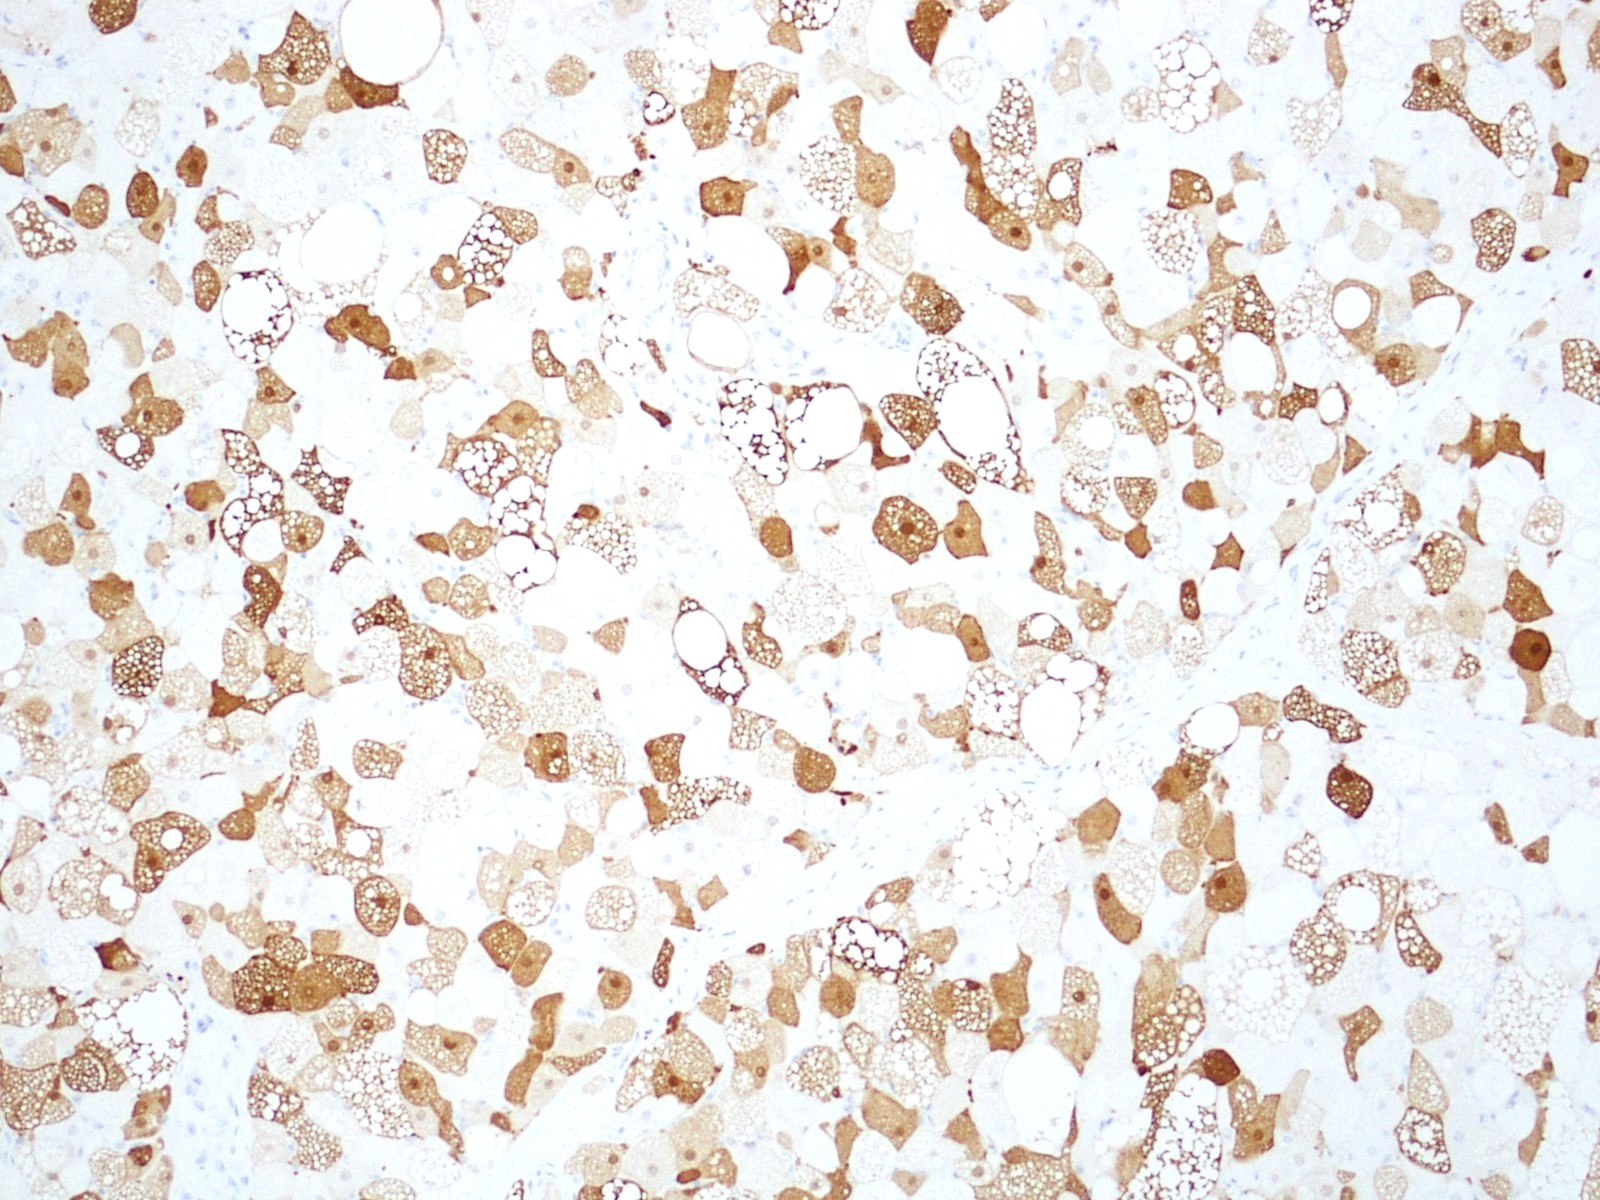

Positive stains

- S100 (Skeletal Radiol 2022;51:1325, J Pathol Transl Med 2017;51:499)

- Ki67 absent to very low (Case Rep Oncol 2017;10:438)

- CD34 (can be positive in spindle cell component) (BMC Surg 2021;21:30)

- Brown fat cells in hibernoma stain strongly with the anti-UCP1 antibody (Clin Sarcoma Res 2019;9:8)

- Periodic acid-Schiff with diastase digestion (PASD) reveals PAS positive, diastase resistant cytoplasmic granules (J Clin Diagn Res 2017;11:ED01)

- CD10 (Hum Pathol 2021;110:12)